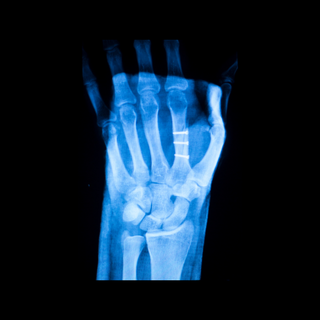

Conditions like fractures, dislocations, and tendon injuries in the hand and wrist require specialized care. Our orthopedic hand surgeons offer expertise in both surgical and non-surgical management of these conditions.